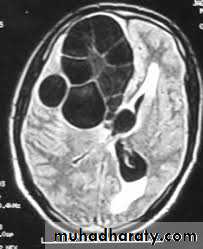

Hydatid cyst

Hydatid cystAppear as large oval hypo dense area density of fluid with well defined margin , sometime at their periphery multiple flecks of calcification are seen at their periphery .

Hydatid cyst with daughter cyst , appear as multiple hypo densities rounded area within the main loculi with multiple rim of

calcification

Hydatid cyst within the liver